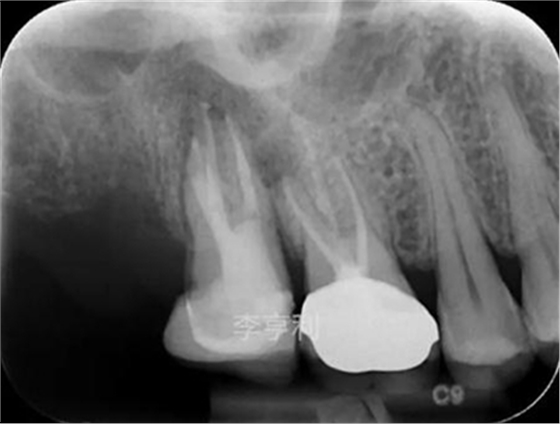

【輔助檢查】: CBCT見17冠部大面積充填物阻射影,接近髓室底,根管內(nèi)充填物錐度尚可,距根尖均為2mm以內(nèi),根尖周大范圍阻射影主要在頰根區(qū)域,波及16的DB根尖區(qū)域,頰腭側(cè)骨板完整